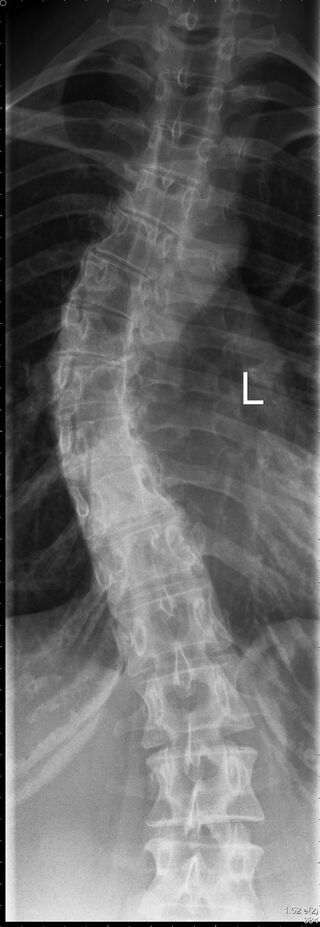

وتتمثل أعراض هذا التشوه العظمي في انحناء العمود الفقري واستدارة الفقرات، وفي بعض الأحيان يتخذ العمود الفقري شكل حرف S أو حرف C، بالإضافة إلى عدم استواء الكتفين وميل الحوض.

وشدد فليشتنماخر على ضرورة عرض الطفل على طبيب عظام في أسرع وقت ممكن، مشيراً إلى أنه يمكن الاستدلال على انحراف العمود الفقري من خلال الأشعة السينية.